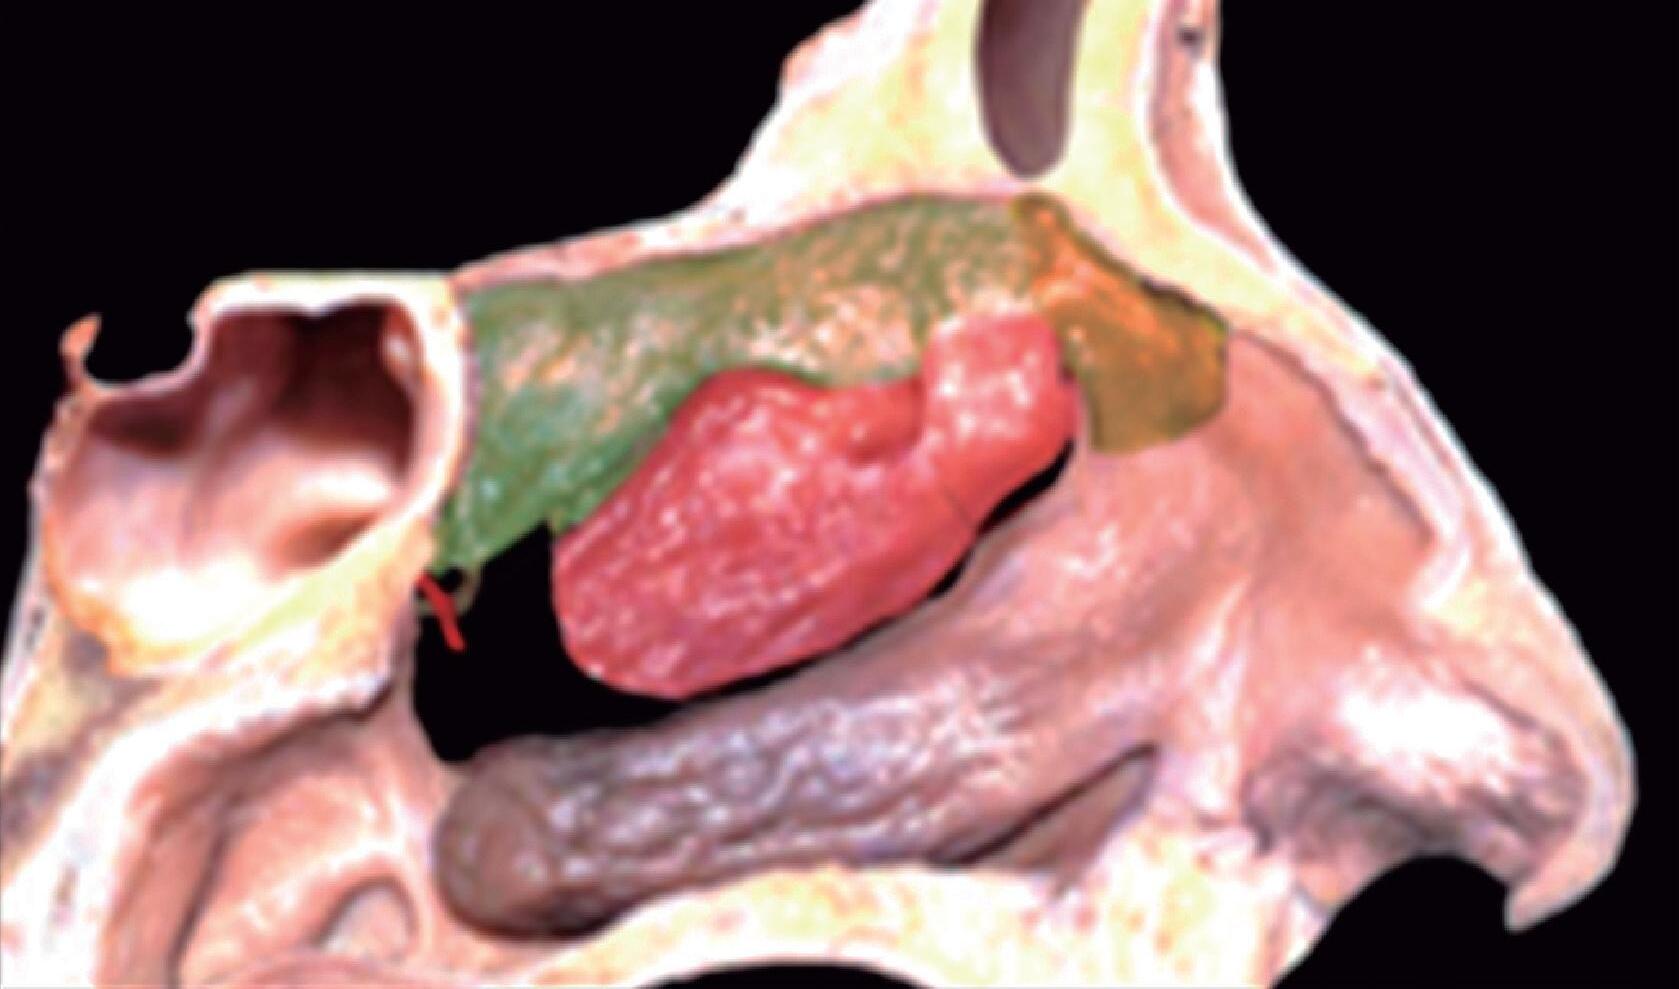

Fig. 1-20. Reconstrução tridimensional de TC demonstrando a lamela basal situada posteriormente à bulha etmoidal, acoplada à parede medial da órbita, fechando a câmara anterior: verde – concha média; vermelho – bulha etmoidal; amarelo – parede medial da órbita; lilás – processo uncinado.

Posterior à bulha etmoidal encontra-se a principal estrutura que fixa a concha média na órbita e na base do crânio: a lamela basal. Esta lamela, como a própria concha média, é oblíqua em relação à lâmina papirácea tanto no sentido anteroposterior como no superoinferior e delimita posteriormente a câmara anterior.

A bulha etmoidal lembra a forma de uma meia-lua e se encaixa na parede medial da órbita (lâmina papirácea) criando, posterossuperiormente (em sua relação com a porção vertical da lamela basal), um recesso algumas vezes chamado de seio lateral e outras de recesso suprabulhar, onde se abrem a própria bulha e cavidades etmoidais vizinhas.